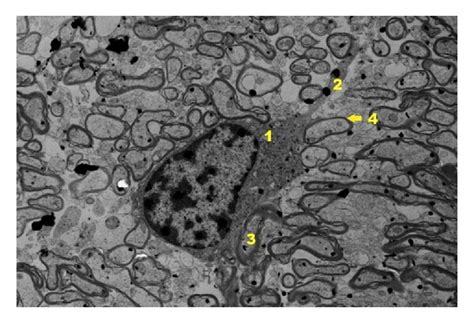

- Hippocampus. There Are No Morphological Changes (a) And Small Rod-like ...